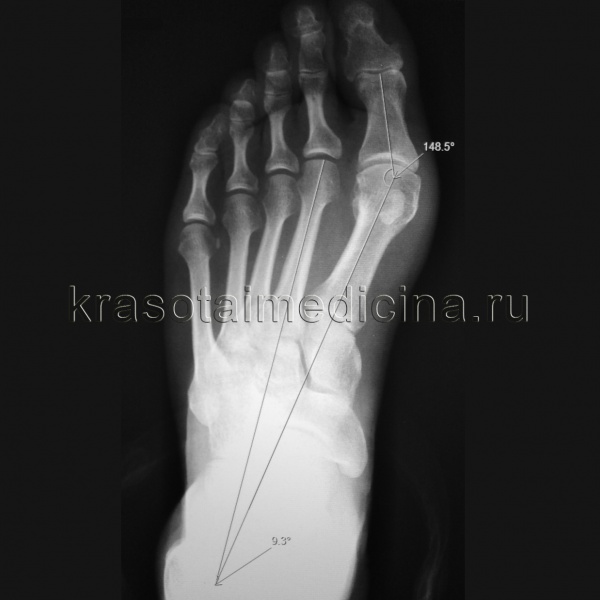

Основная цель операции заключается в возвращении измененного угла первой плюсневой кости в физиологически правильное положение с помощью специальных винтов. В случае запущенной стадии заболевания дополнительно производится коррекция других деформированных пальцев и исправление искривлений.

Вальгусная деформация стопы — это медицинское обозначение данной проблемы. Искривленный вовнутрь большой палец и нарастающая с течением времени шишка причиняют боль и дискомфорт. В результате человек начинает испытывать трудности с выбором обуви, поражаются сухожилия и ткани, возникает разрушение костной структуры, сказывающееся на кровообращении.